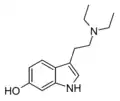

| Chemical structure | Short Name | Origin | Ring Substitution | RN1 | RN2 | Full Name | CAS Number |

|---|---|---|---|---|---|---|---|

| Tryptamine | Animals, plants, fungi | H | H | H | 3-(2-aminoethyl)indole / 2-(1H-indol-3-yl)ethanamine | 61-54-1 |

| NMT | Plants | H | H | CH3 | N-methyltryptamine | 61-49-4 |

| 2-HO-NMT | Plants | 2-OH | H | CH3 | 2-hydroxy-N-methyltryptamine | 106987-89-7 |

| 5-MeO-NMT | Plants | 5-OCH3 | H | CH3 | 5-methoxy-N-methyltryptamine | 2009-03-2 |

| Serotonin | Animals, plants | 5-OH | H | H | 5-hydroxytryptamine | 50-67-9 |

| Nω-Methylserotonin (norbufotenin) | Plants | 5-OH | H | CH3 | 5-hydroxy-N-methyltryptamine | 1134-01-6 |

| Bufotenin | Animals, plants, fungi | 5-OH | CH3 | CH3 | 5-hydroxy-N,N-dimethyltryptamine | 487-93-4 |